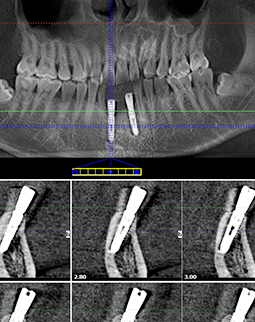

这是我种牙后的第二天,麻药退去了,还是有些不舒服,昨天种完牙一直咬了40分钟左右的棉球,现在还是有点渗血,多少有点疼,客服刚给我致电,告诉我不要吐口水,不然会加重出血量。昨天种好牙到现在,我吃了两餐饭了,然后漱了下口,我告诉你们,种完牙不能马上就刷牙。距离昨天手术过去了24小时,我到现在创口没有肿胀,现在就希望快点愈合。有人担心“种植牙有危险,种植牙会出很多血,种植牙创口会很大”,我问医生要了我的CT和种牙口内照,想给大家看一下。

左边是我种牙之前,缺牙很久了,所以这个牙床口长好了。右边是我的种植牙创口,大小和牙根差不多,这个很容易理解,因为种植体就是人造牙根,得有个洞才能把它埋进去,我种牙的创口很小了,基本是微创的,比起过去的切开牙龈种牙好太多了!所以大家不用太担心,你选个好的医院和医生,种植牙还是很靠谱的。